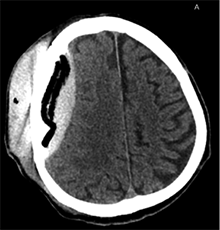

Po pusės metų vyras konsultuotas ambulatoriškai planine tvarka. Atlikus GKT, nustatyta nedidelė lėtinė SDH dešinėje pusėje parietaliai. Po mėnesio suplanuota atlikti KP. Operacijos metu suformuotas kranioplastikos lopas (KPL) iš kraniocemento. Atlikta daugybinių KPL perforacijų (6 pav.), KPL fiksuotas prie kaukolės 10 siūlių. Kitą dieną po operacijos atlikta kontrolinė GKT (7 pav.): po KPL nustatyta hemostatinė medžiaga ir ~20 mm storio ūminė epidurinė hematoma. Vidurio struktūrų dislokacija į kairę – iki 3 mm. Dešinėje pusėje, poodyje – pooperacinė sankaupa su pakraujavimu. Tą pačią dieną atlikta skubi operacija epidurinei ir periostinei hematomoms pašalinti. Aktyvaus kraujavimo operacijos metu nenustatyta. KPL grąžintas, minkštieji audiniai susiūti (8 pav.). Po operacijos paciento būklė buvo stabili, patologinių neurologinių simptomų nenustatyta. Praėjus 2 savaitėms, esant sklandžiai pooperacinei eigai, vyras perkeltas į slaugos ligoninę.

7 pav. Po ketvirtosios operacijos (kranioplastikos) (kraniolopo padėtis gera; po kraniolopu ūminė EDH su hemostatine medžiaga, VSD į kairę – iki 3 mm; dešinėje – poodyje pooperacinė sankaupa su pakraujavimu)